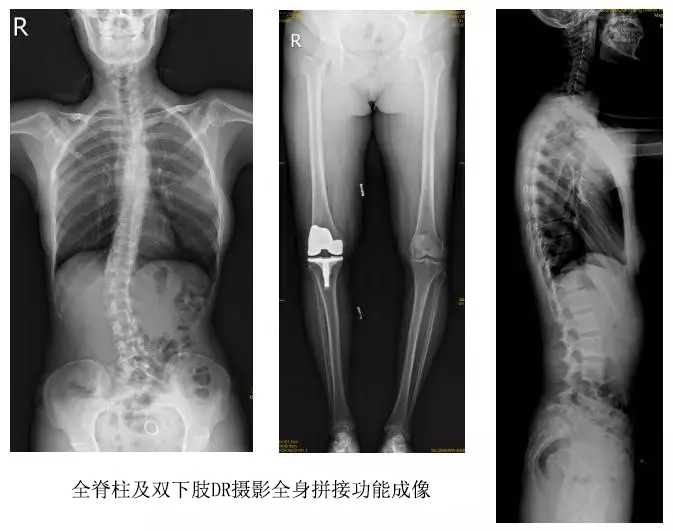

以某院所攝X光片為例,對比傳統攝片與全身拼接功能的區別:

傳統X光片只能觀察每個部位的局部情況,無法在統一體上進行連續、全面的觀察,全脊柱及下肢全長片則能直觀的看到整體形變。通過DR全身拼接功能實現的完整成像,為診治脊柱及下肢畸形提供了完美的臨床影像依據,對臨床診斷、術前手術方案的制定和術后療效的評估等臨床應用具有十分重要的意義,有效滿足了此類疾病臨床診斷和治療的要求。